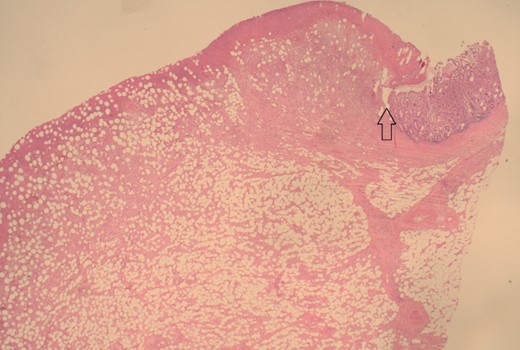

The patient was taken to the theatre for an emergency laparotomy. Intraoperative findings were of high-grade SBO, secondary to terminal ileal intussusception. The involved small bowel was viable with no perforation. The intussusception was reduced. Nidus was an intraluminal polypoid lesion. A small bowel resection and a primary, double-layered hand-sewn anastomosis were performed. A specimen was sent for histology. Histology confirmed an ulcerated benign submucosal lipoma (45 × 30 × 22 mm) as the cause (Figs 4–7).

12.5× magnification showing the intact surface small bowel mucosa with the underlying lipoma.

12.5× magnification showing the junction between the ulcerated leading point of the intussusception on the left and the preserved mucosa on the right of the arrow.